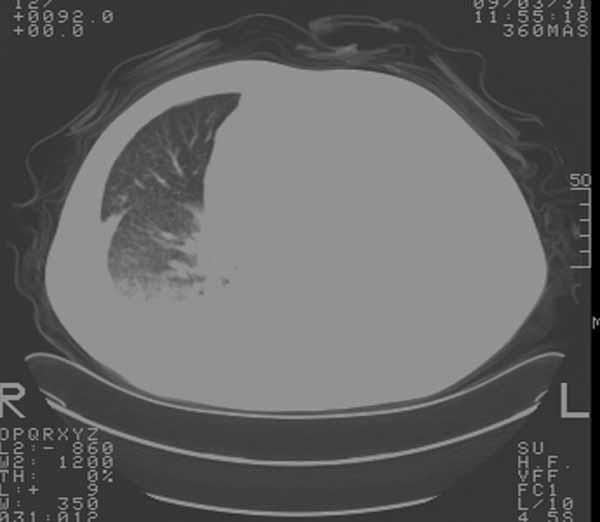

以下是引用余辉在2009-3-31 18:43:00的发言:[br]肺水肿,双侧心腔积液,心包积液,心影增大,疑似心衰

以下是引用wangyong1977在2009-3-31 20:46:00的发言:[br]肺水肿,双侧胸腔积液,心包积液,心影增大,疑似心衰 [br]

以下是引用宇宙ct在2009-3-31 18:57:00的发言:[br]肺水肿,双侧心腔积液,心包积液,心影增大,疑似心衰 [br] [br]